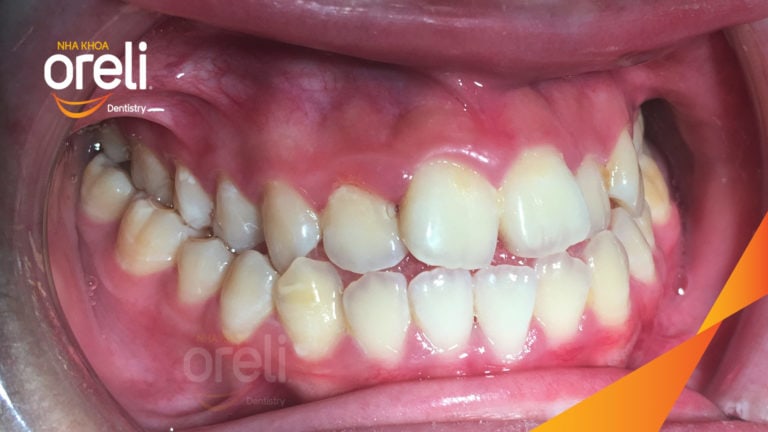

Niềng răng lệch khớp cắn tại Buôn Ma Thuột – Hành trình thay đổi nụ cười tại Nha khoa Oreli Niềng răngMóm Xem thêm